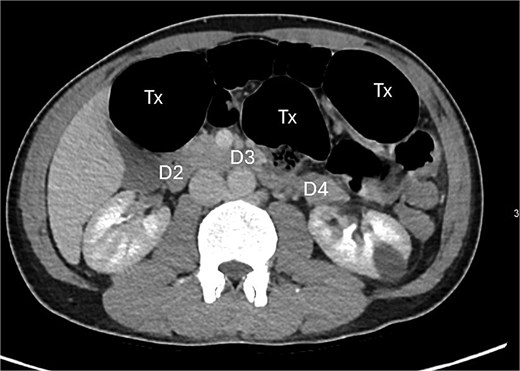

A contrast-enhanced computed tomography (CT) scan of the abdomen and pelvis demonstrated a large bowel obstruction with a transition point at the distal transverse colon with swirling of the mesentery. Downstream large bowel was collapsed. Upstream dilatation included the terminal ileum suggested an incompetent ileo-caecal valve. The gastric antrum was also involved in the internal hernia, resulting in gastric outlet obstruction. See Figs 1–5.

Posterior displacement of the duodenum (D4) due to herniated transverse colon.